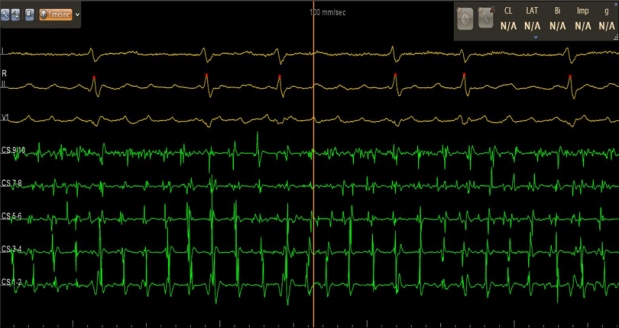

团队核心电生理术者——张伟在回顾该病例时指出,本次手术全程0射线,依赖超声自动建模,实现了“绿色”电生理操作。整台手术耗时约1.5小时,其中肺静脉隔离关键步骤仅需约20分钟。患者术后恢复良好,次日即可下床活动,真正体现了“高效、安全、微创”的现代治疗理念。

术后转窦律图